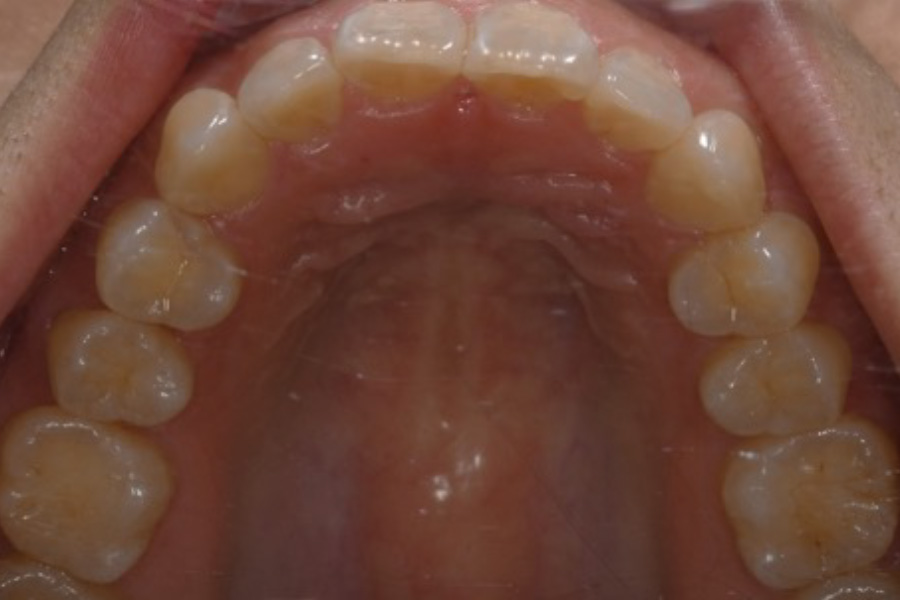

治療前

治療後

主訴 歯並びを治したい

期間 5か月

費用 マウスピース矯正(キャンペーン)

434,000円(税込)

治療内容 目立ちにくいマウスピース矯正(非抜歯矯正)

歯と歯の間に隙間をつくることにより、歯列弓を広げながら治療を行いました。